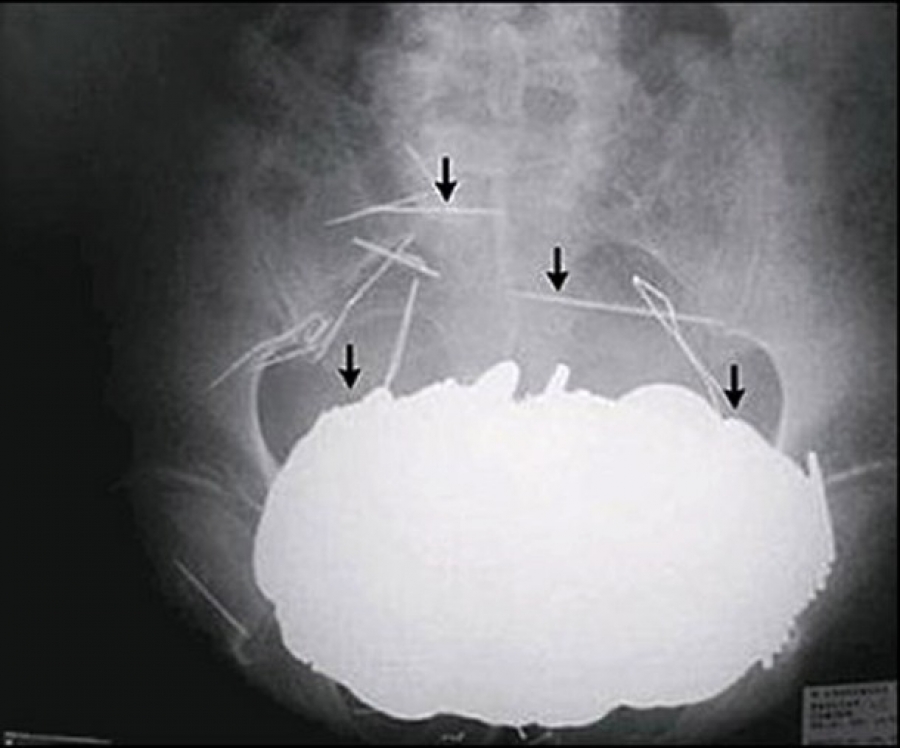

проглотил стекло

Что будет если случайно проглотил стекло 107 фотографий